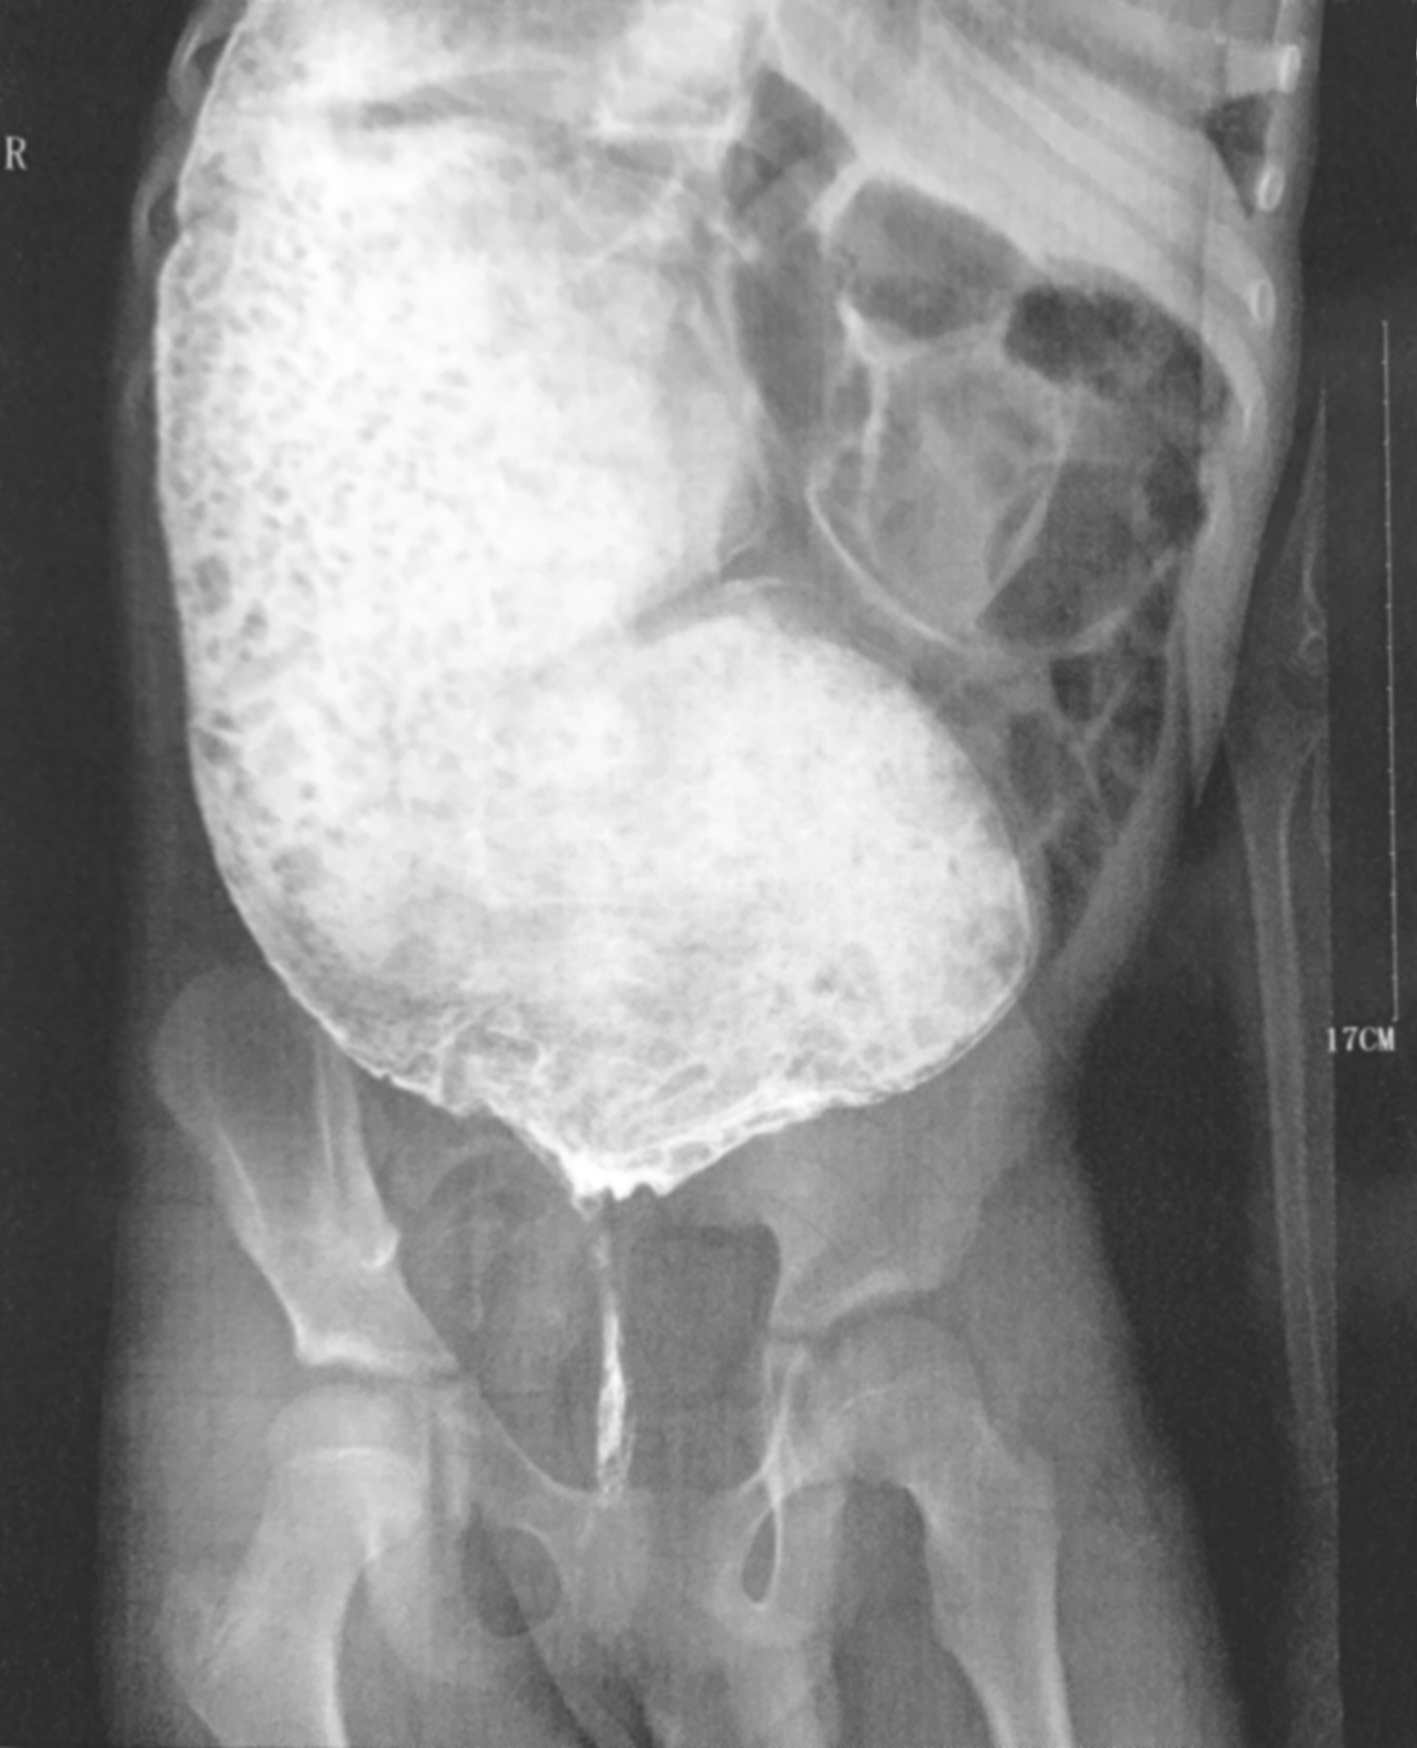

不同类型的HD钡剂灌肠检查的表现亦不同,见图3-3~图3-9。

图3-8 全结肠型先天性巨结肠症钡剂灌肠

结肠充稀钡后整段结肠无明显扩张。